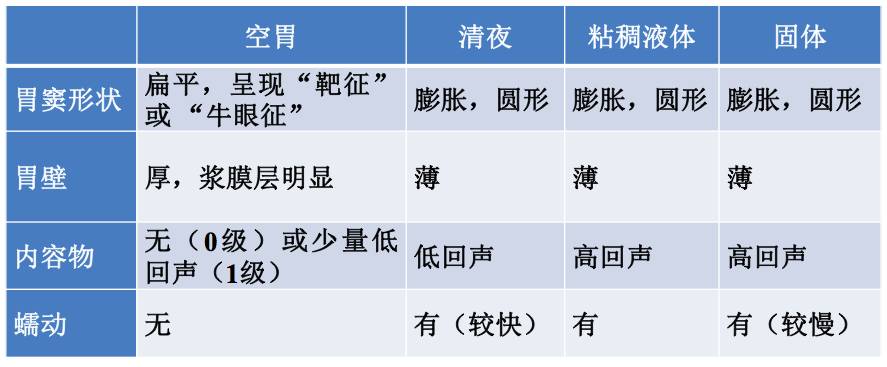

?空胃

?清亮无渣液体

?粘稠液体

?固体

空胃

胃成扁平状,前后壁彼此贴近,呈现“靶征”或者卵圆形的“牛眼征”

胃成扁平状,前后壁彼此贴近,呈现“靶征”或者卵圆形的“牛眼征”

清亮无渣液体

?胃壁逐渐变薄,胃窦膨胀,形状近似圆形

?均匀一致的低回声

?低回声液体中掺杂高回声的空气气泡,称为“满天星”

粘稠液体如牛奶

?胃壁变薄,胃窦膨胀,形状近似卵圆形

?为均匀一致的高回声

固体食物

(A)初期5min:“磨玻璃样”,胃前壁呈高回声线性结构,影响深部组织的超声影像采集

(B)90min后:混合性强回声